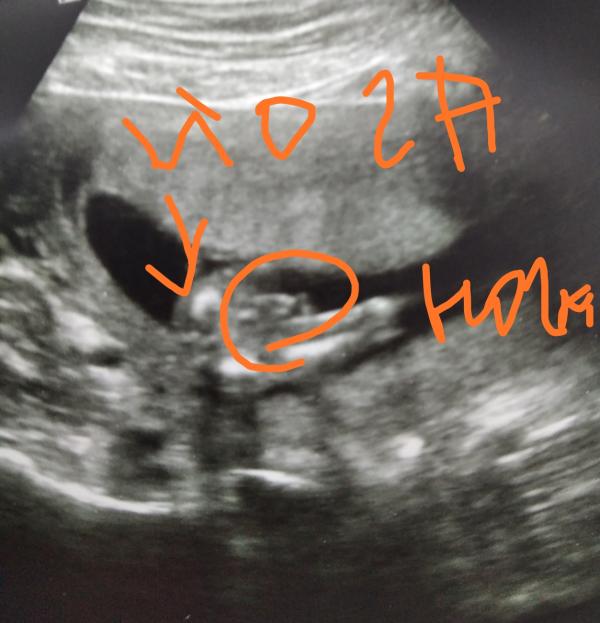

post image 2

Есиь специалисты УЗИ? мальчик или девочка?врач сначала сказала девочка,потом сказала все таки мальчик.срок 15 недель

Мальчик!)

Мальчик

На пипку похоже)

А точно мальчик? Это не ножку согнул левую?

Мальчик ) хоть я и не специалист узи